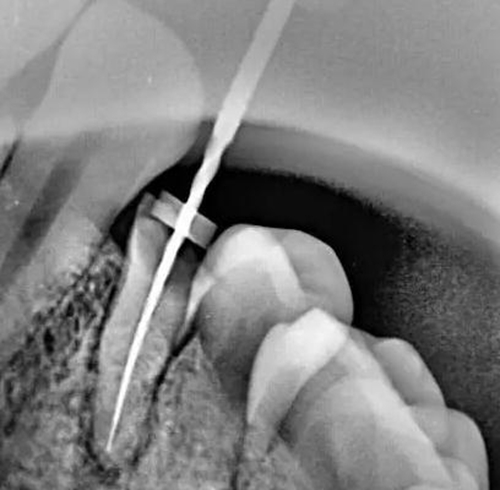

牙根內(nèi)外吸收的原因不同,治療方法和預(yù)后也不一樣。因此,應(yīng)根據(jù)X線(xiàn)和臨床表現(xiàn),區(qū)別內(nèi)外吸收,選擇適應(yīng)的治療方法,用X線(xiàn)根尖片和咬合片的表現(xiàn)區(qū)分牙根內(nèi)外吸收;內(nèi)吸收邊界清楚光滑,形狀多對(duì)稱(chēng),吸收部位根管粗大;外吸收邊界粗糙,密度不一,呈蠶食壯,形狀多不對(duì)稱(chēng),在破壞未穿通根管前,仍能尋找到根管的原始輪廓。偏移投照時(shí),內(nèi)吸收與根管的位置關(guān)系不變,而外吸收部位發(fā)生變化。

內(nèi)吸收是從髓腔或根管內(nèi)壁開(kāi)始,與牙髓炎癥和細(xì)菌感染有關(guān)。一般無(wú)癥狀,多為X線(xiàn)照相時(shí)發(fā)現(xiàn)。應(yīng)盡早行根管治療,去除感染組織后,預(yù)后良好,否則進(jìn)一步發(fā)展會(huì)造成根管壁的穿孔。徹底去除內(nèi)吸收部位的感染組織較為困難,充分沖洗或超聲蕩洗是有效的清潔方法,并在根管內(nèi)封Ca(OH)2蝴劑1周后再根充。由于內(nèi)吸收過(guò)大,根管壁很薄,應(yīng)避免過(guò)大壓力,要選用Ca(OH)2基質(zhì)的蝴劑與牙膠根充,根管壁穿孔較小,可用 Ca(OH)2糊劑根充3個(gè)月,誘導(dǎo)硬組織形成后再根充;或用根管水泥(MTA)根管內(nèi)根充并修補(bǔ)。較大的根管壁穿孔可用MTA從根管內(nèi)或手術(shù)修補(bǔ)。內(nèi)吸收近根尖區(qū)可考慮根尖手術(shù),多根牙可考慮截根術(shù)。